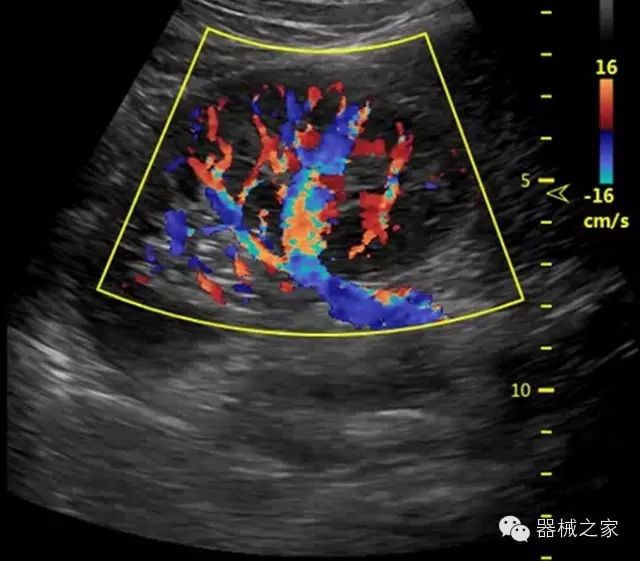

臨床圖片賞析

·獨有的RF平臺提高微小細節(jié)顯示、圖像對比度和邊界清晰度;

·特有的XCEN探頭,超寬的帶寬,表現(xiàn)更高分辨率和對比度;

·單晶純凈波探頭提供更佳的穿透力和彩色敏感度;

·完整的3D/4D臨床應(yīng)用,STIC, MCUT 和Auto NT等滿足產(chǎn)科所有應(yīng)用;

·獨有RF敏感血流使得心臟血流完美呈現(xiàn);